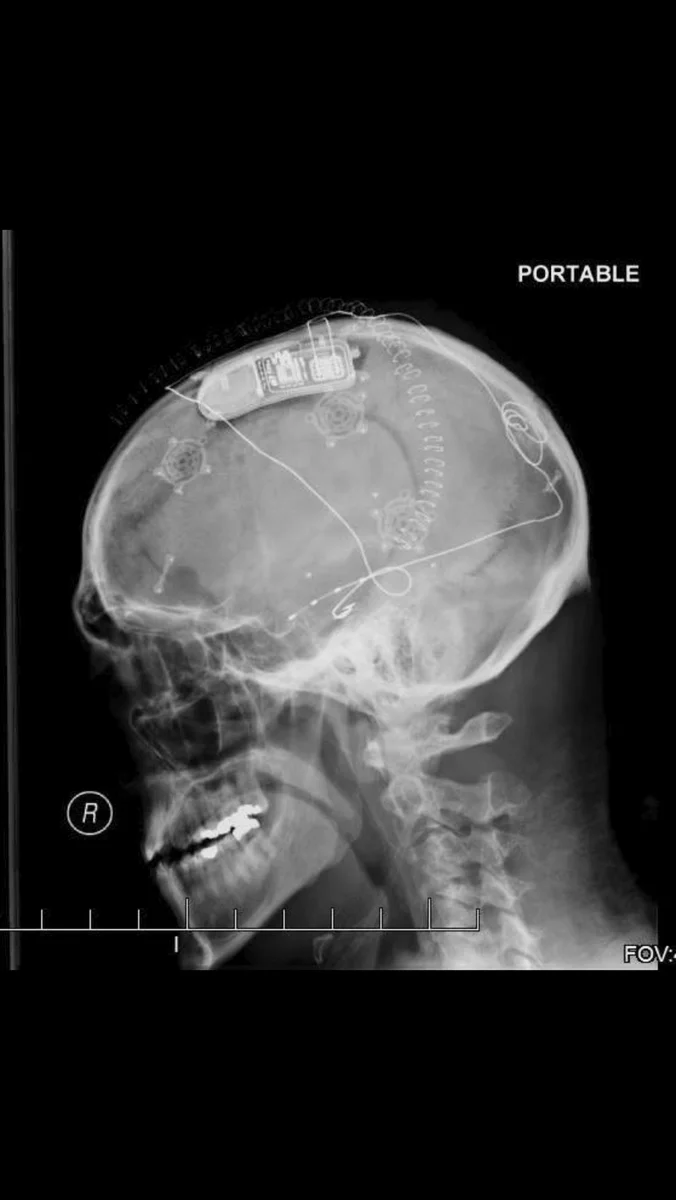

Система нейростимуляции для профилактики эпилептических приступов